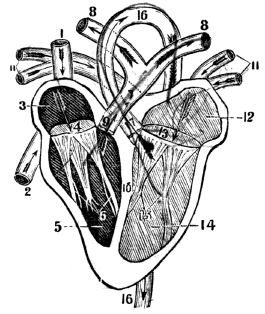

| 17. | Anatomy of the Circulatory Organs, | 154 |

| 18. | Physiology of the Circulatory Organs, | 164 |

| 19. | Hygiene of the Circulatory Organs, | 172 |